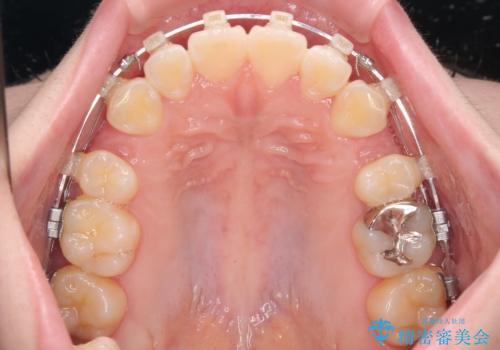

- 矯正装置

- クリアブラケット

- 1年8ヶ月

- くちばしのように飛び出した前歯を気にして来院された患者様です。

上下左右の第一小臼歯4本を抜歯して、ワイヤー装置にて矯正治療を行うこととしました。

舌の突出癖により、口元が突出しているだけでなく、上下前歯が非接触となっておりました。

舌のトレーニングをしっかりと行っていただくことで、2年を切って治療を終えるとともに

、上下前歯を接触させることができました。